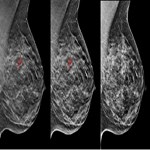

سرطان پستان: دویدن بهتر از راه رفت است

نتایج مطالعات پیشین نشان داد که پرداختن به مقادیر توصیه شده فعالیت ورزشی ( اجرای 5/2 ساعت فعالت ورزشی با شدت ...